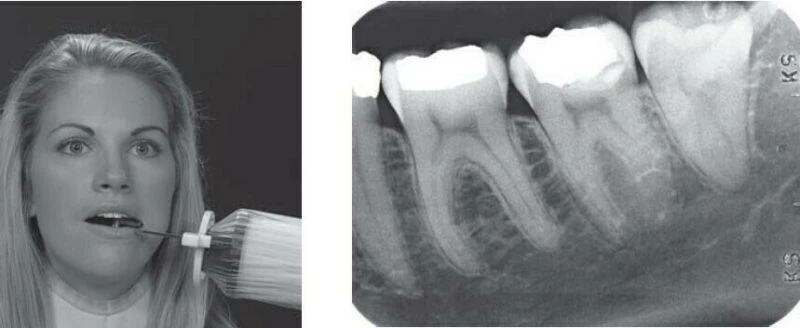

Điều này thể hiện rõ nhất là Cruxell có nhiều kích thước phim từ nhỏ đến lớn, phù hợp với mọi khuôn miệng và độ tuổi của bệnh nhân. Chất liệu phim “thân thiện” với người dùng, hoàn toàn không gây kích ứng cho bệnh nhân và chỉ mất vài giây để hiển thị sau khi bác sĩ hay kỹ thuật viên đưa phim vào.